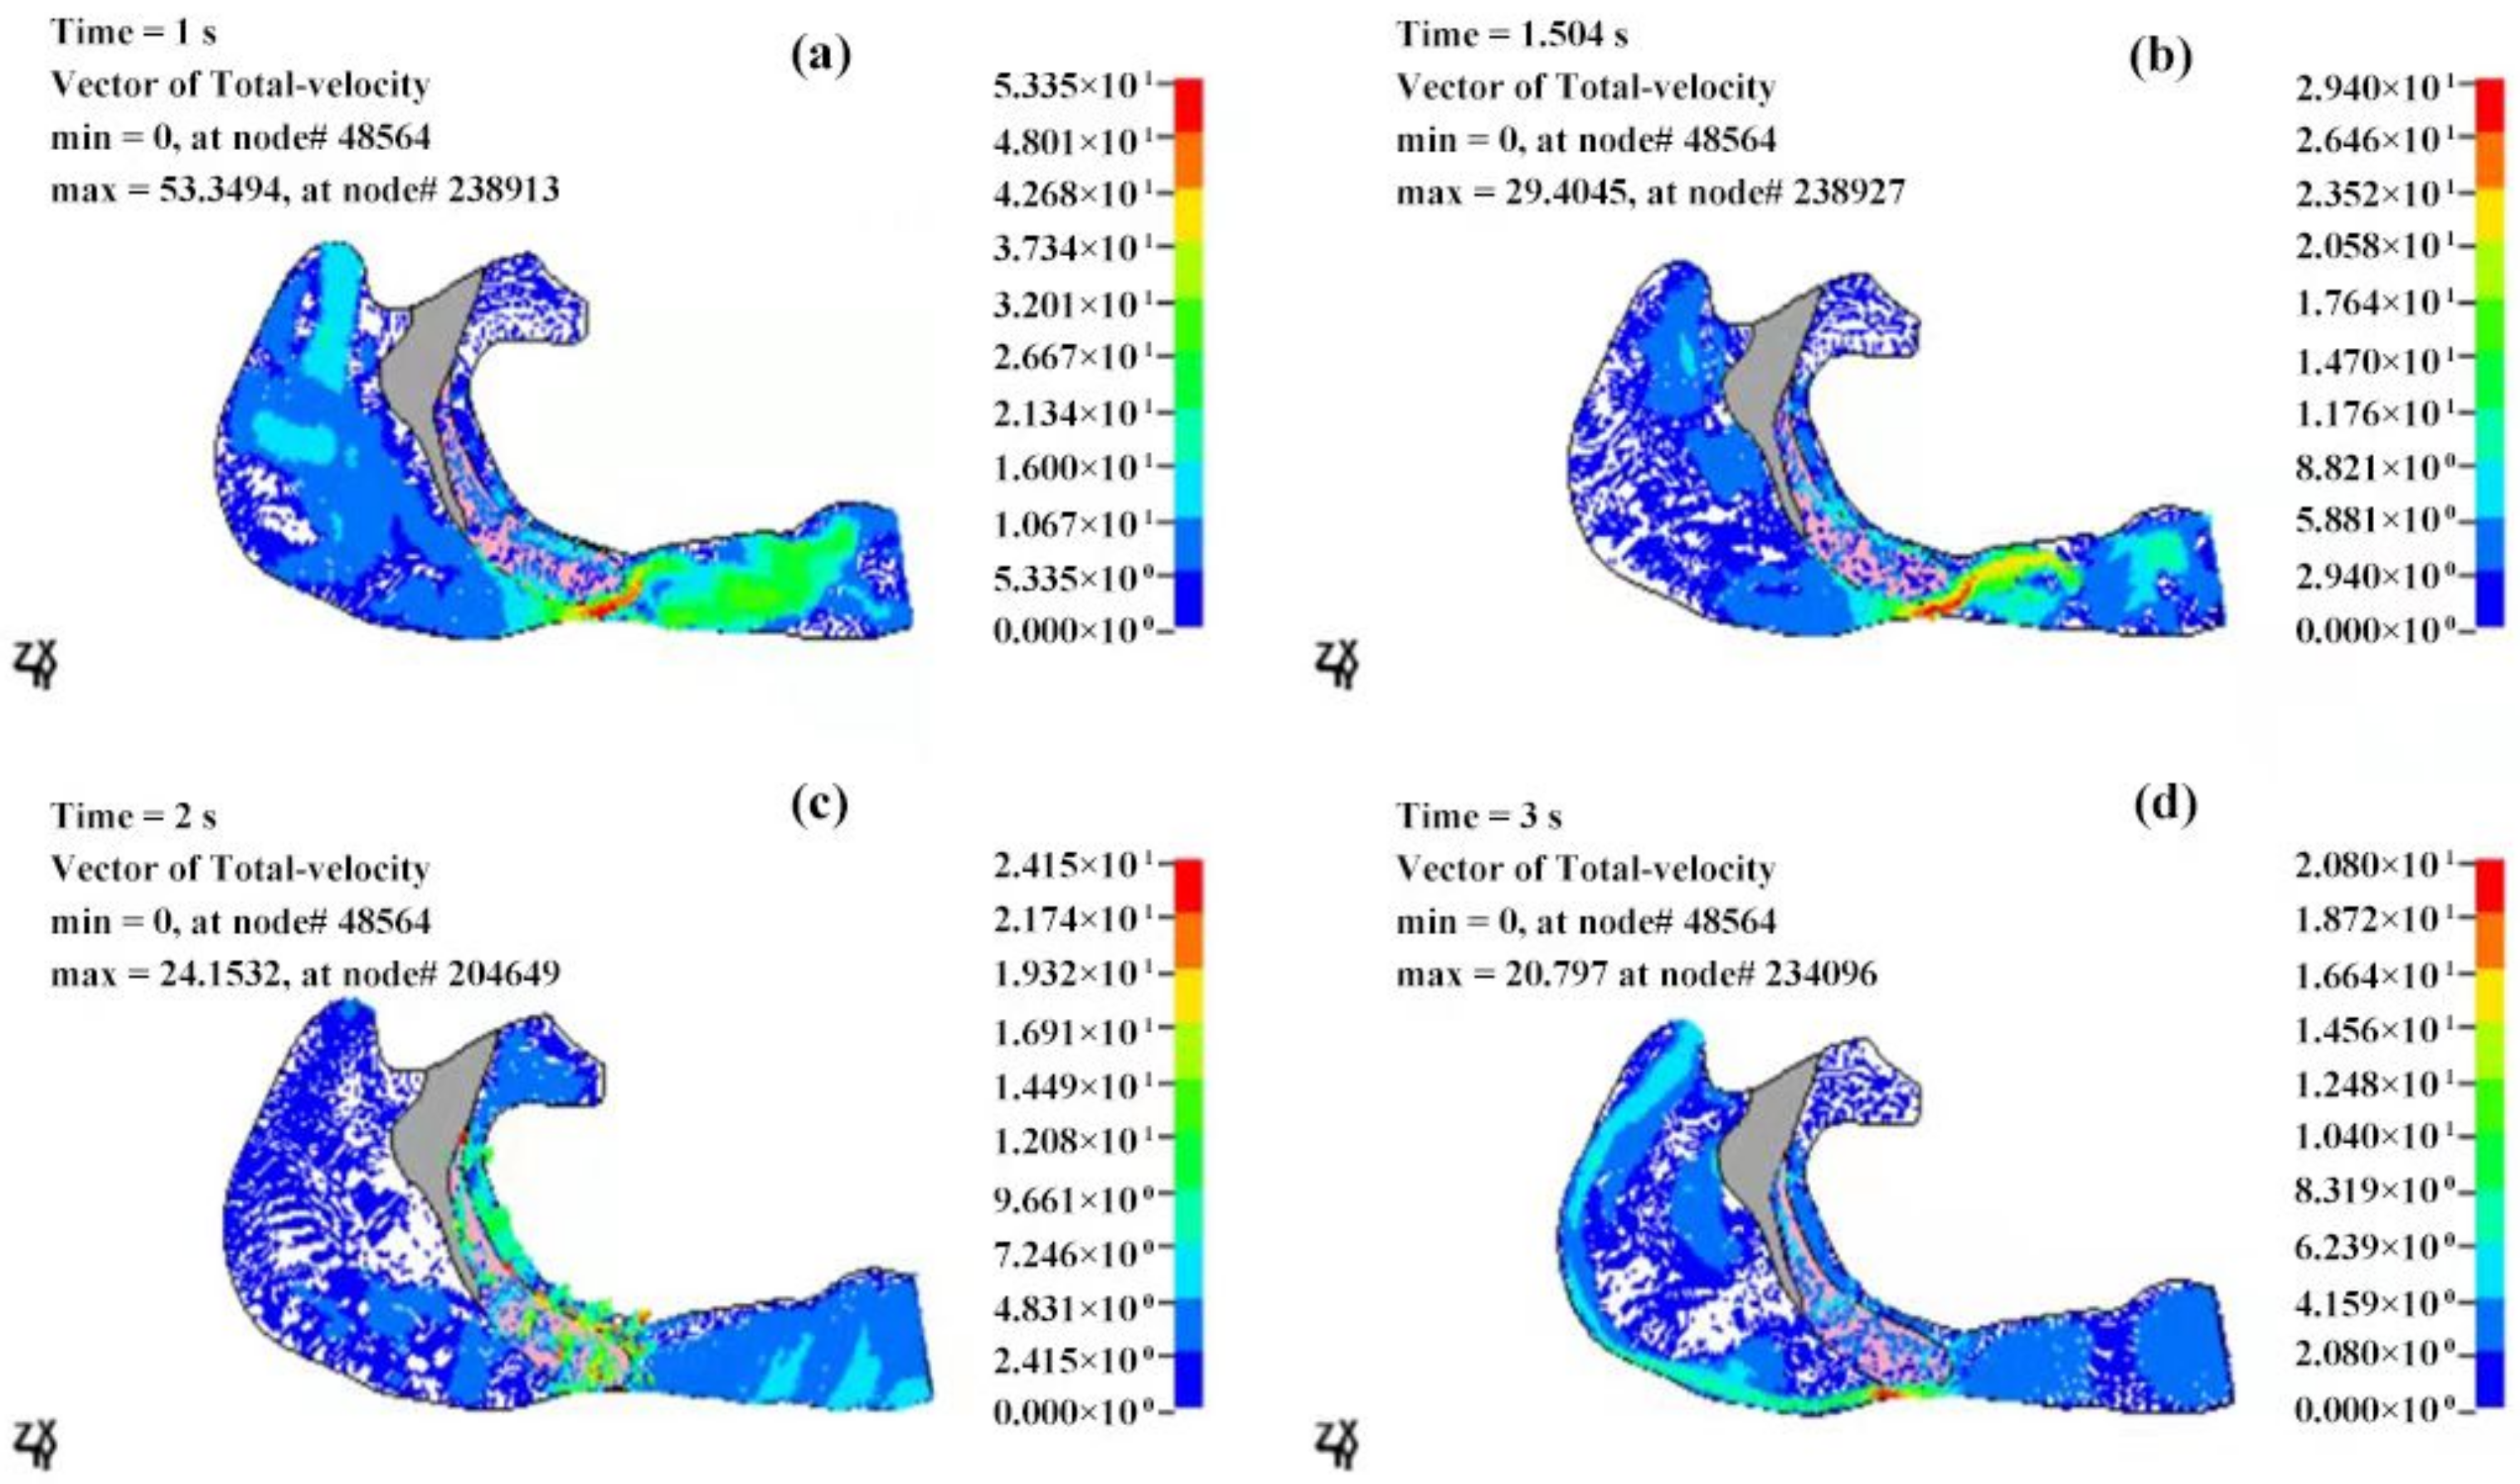

3.2.2. Velocity Field of the Cavity

4. Discussions

- The airflow characteristics during the inhalation phase are noticeably different from those in the exhalation phase for both eupnea and apnea. As the OSAHS patient breathes, the minimum pressure occurs alternately between the soft palate and the anteroposterior wall of pharynx, which causes the soft palate to vibrate during respiration, and therefore, the patient snores in sleep.

- The mechanical environment of the airway is directly dependent on the action of the airflow. If the mechanical properties of the soft palate remain unchanged, the pressure makes the soft palate collapse in apnea. In eupnea, the pressure allows the airflow to pass freely through the airway.